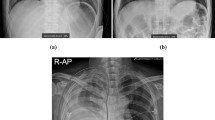

All CXRs scanned by the computed radiography (CR) or digital radiography (DR) system were downloaded from PACS at ASAN Medical Center. From the 491,845 CXRs images, 9792 images were selected depending on the availability of corresponding chest CT images from January 2011 to November 2016. This dataset was derived from approximately 2 million digital imaging and communications in medicine images from the initial examination of normal and abnormal CXRs identified by hospital diagnostic code. Raw datasets extracted PACS system included the bone, MRI, skull, and others. We cleansed these types for CXRs. Generating a strong label during a short period in a hospital is difficult. We decided on the optimal number of datasets for training and then drew it directly for the radiologist. We developed in-house software for delineating the ROIs as a reference mask for the diseased lesions so that the in-house radiologists could efficiently draw the ROIs on the lesions with existing software over many CXRs. This software included shortcuts for mapping and loading of the next image and a user interface for auto-loading the images, moving an image to the trash, auto-saving, and annotating an ROI. Two thoracic radiologists, with five and ten years of experience, shared their opinions before labeling the diseased lesions. Normal and abnormal datasets with nodules (N including mass)/consolidation (C) or interstitial opacity (IO) were confirmed by chest CT. For pleural effusion (PLE) and pneumothorax (PN), detected via CXRs, confirmation was reached through consensus of two thoracic radiologists with corresponding chest CT images due to the difficulty of detecting PLE and PN in CXRs. Thereafter, two thoracic radiologists delineated the exact boundaries of the lesions using our software. If co-located lesions were observed in the CXRs, the separated boundaries of overlapped shapes in CXRs were drawn by thoracic radiologists. The study design’s drawing of the ROIs for one of the five disease patterns of lesions, by simultaneously referring to the patients’ paired computed tomography images, is shown in Fig. 2. The number of normal and abnormal CXRs was 6068 and 3724, respectively. The number of CXRs with N, C, IO, PLE, and PN patterns was 944 (1092), 550 (721), 280 (538), 1361 (1661), and 589 (622), respectively. The bracket refers to the number of references drawn by two thoracic radiologists. To detect the five disease patterns, all CXRs were randomly split into training, tuning, and test sets in 70:10:20 ratios as for final CAD assessment with initial CXRs (Table 1). To evaluate the reproducibility of CAD, follow-up CXRs within one week with little change of lesions were selected in the entire follow-up CXRs. Table 2 shows the paired datasets for the initial and follow-up CXRs extracted from the test datasets of Table 1, which were confirmed by expert thoracic radiologists. The average intervals between the initial and follow-up CXRs were: N (2.09 ± 1.33), C (1.33 ± 1.15), IO (2.33 ± 2.21), PLE (1.63 ± 1.69), and PN (1.67 ± 2.18). Despite the lack of change according to the pattern of the lesion between the paired initial and follow-up CXRs, these datasets may differ in their image quality, angle, and position (Fig. 3).

Representative examples of initial chest radiographs (CXRs) taken from each patient within a short-term interval (up rows), follow-up images of CXRs taken from each patient within a short-term interval (middle rows), and gold-standards labeled by two thoracic radiologists (bottom rows). N nodule, C consolidation, IO interstitial opacity, PLE pleural effusion, PN pneumothorax in Fig. 2.